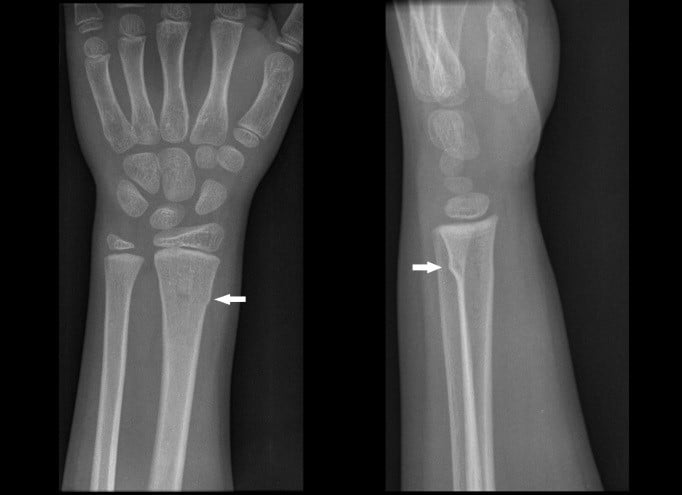

Buckle Fracture Symptoms Causes Treatment 2025, Buckle fracture of the wrist CUH 2025, Buckle Fracture Raleigh Hand Surgery Joseph J. Schreiber MD 2025, Fracture How to treat a buckle fracture of the distal radius 2025, Torus fracture Wikipedia 2025, Buckle fracture 2025, Kidshealth Buckle Fractures Akron Children s 2025, Buckle fractures of the distal radius in children CMAJ 2025, How to Care for Your Child with Buckle Fracture Sidra Medicine 2025, Kids Health Information Fracture care buckle injury 2025, The Pediatric Wrist Buckle Fracture is Common Louisville Bones 2025, Buckle fracture 2025, Forearm Fractures Children s Mercy Kansas City 2025, Buckle Fracture Raleigh Hand Surgery Joseph J. Schreiber MD 2025, Buckle Fractures Rady Children s Hospital 2025, Greenstick Buckle Fracture Activate Physiotherapy 2025, What are Buckle Fractures WristSupports 2025, Buckle Greenstick Fracture of the Distal Radius Sports 2025, Choosing Wisely Distal Radius Buckle Fractures CanadiEM 2025, Buckle Greenstick Fracture of the Distal Radius Sports 2025, Clinical Practice Guidelines Distal radius and or ulna 2025, Buckle fracture Radiology at St. Vincent s University Hospital 2025, Radiology Case 5 SpringerLink 2025, Buckle fracture of the wrist Resource Library Sheffield 2025, Forearm Fractures Children s Mercy Kansas City 2025, Buckle fracture Radiology Case Radiopaedia 2025, Fracture How to treat a buckle fracture of the distal radius 2025, Buckle fracture in a girl age 2 years 3 months who presented to 2025, Greenstick Fracture or Paediatric Fracture Treatment 2025, Buckle fracture Radiology Case Radiopaedia 2025, Buckle Fracture by Dr. David Nelson MD 2025, Pondering Paeds Buckle In 2025, State of the Art Pediatrics Buckle Fractures in Children 2025, OrthoKids Forearm Fractures 2025, Buckle Greenstick Fracture of the Distal Radius Sports 2025.

Buckle Fracture Symptoms Causes Treatment 2025, Buckle fracture of the wrist CUH 2025, Buckle Fracture Raleigh Hand Surgery Joseph J. Schreiber MD 2025, Fracture How to treat a buckle fracture of the distal radius 2025, Torus fracture Wikipedia 2025, Buckle fracture 2025, Kidshealth Buckle Fractures Akron Children s 2025, Buckle fractures of the distal radius in children CMAJ 2025, How to Care for Your Child with Buckle Fracture Sidra Medicine 2025, Kids Health Information Fracture care buckle injury 2025, The Pediatric Wrist Buckle Fracture is Common Louisville Bones 2025, Buckle fracture 2025, Forearm Fractures Children s Mercy Kansas City 2025, Buckle Fracture Raleigh Hand Surgery Joseph J. Schreiber MD 2025, Buckle Fractures Rady Children s Hospital 2025, Greenstick Buckle Fracture Activate Physiotherapy 2025, What are Buckle Fractures WristSupports 2025, Buckle Greenstick Fracture of the Distal Radius Sports 2025, Choosing Wisely Distal Radius Buckle Fractures CanadiEM 2025, Buckle Greenstick Fracture of the Distal Radius Sports 2025, Clinical Practice Guidelines Distal radius and or ulna 2025, Buckle fracture Radiology at St. Vincent s University Hospital 2025, Radiology Case 5 SpringerLink 2025, Buckle fracture of the wrist Resource Library Sheffield 2025, Forearm Fractures Children s Mercy Kansas City 2025, Buckle fracture Radiology Case Radiopaedia 2025, Fracture How to treat a buckle fracture of the distal radius 2025, Buckle fracture in a girl age 2 years 3 months who presented to 2025, Greenstick Fracture or Paediatric Fracture Treatment 2025, Buckle fracture Radiology Case Radiopaedia 2025, Buckle Fracture by Dr. David Nelson MD 2025, Pondering Paeds Buckle In 2025, State of the Art Pediatrics Buckle Fractures in Children 2025, OrthoKids Forearm Fractures 2025, Buckle Greenstick Fracture of the Distal Radius Sports 2025.